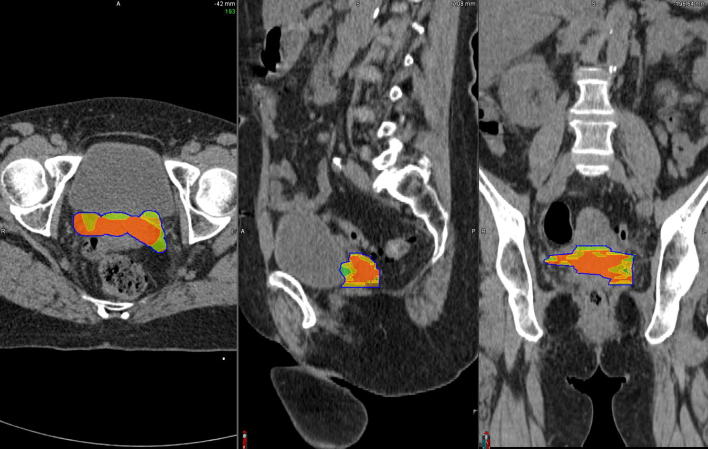

3.3. Coverage of the initial high-uptake sub-volume (V1) by CTV-HR

When considering patients who relapsed, V1 was not included in the CTV-HR in 40.5% of patients and not covered by the 85 Gy, neither by the 80 Gy isodose in 17/42 patients (40.5%) and 7/42 patients (16.7%), respectively (examples in Fig. 2). The mean inclusion of V1 in CTV-HR was 90.3 ± 13.9% (Fig. 3) and the coverage of V1 by the 85 Gy (Fig. s1A, supplementary material), 80 Gy (Fig. s2A, supplementary material), and 78 Gy (Fig. s3A, supplementary material) isodoses were 92.1 ± 12.1%, 98.4 ± 4.0% and 100%, respectively.

Fig. 2.

Examples of brachytherapy planning in 2 different patients who experienced distant relapse. In these 2 cases, the entire V1 (green) was not included in the CTV-HR (magenta volume) and not covered by the D2eq = 85 Gy (red), neither by the 80 Gy isodose (orange). It was however included in the CTV IR (blue volume) and covered by the 78 Gy (cyan) and 65 Gy isodoses (green). (For interpretation of the references to colour in this figure legend, the reader is referred to the web version of this article.)